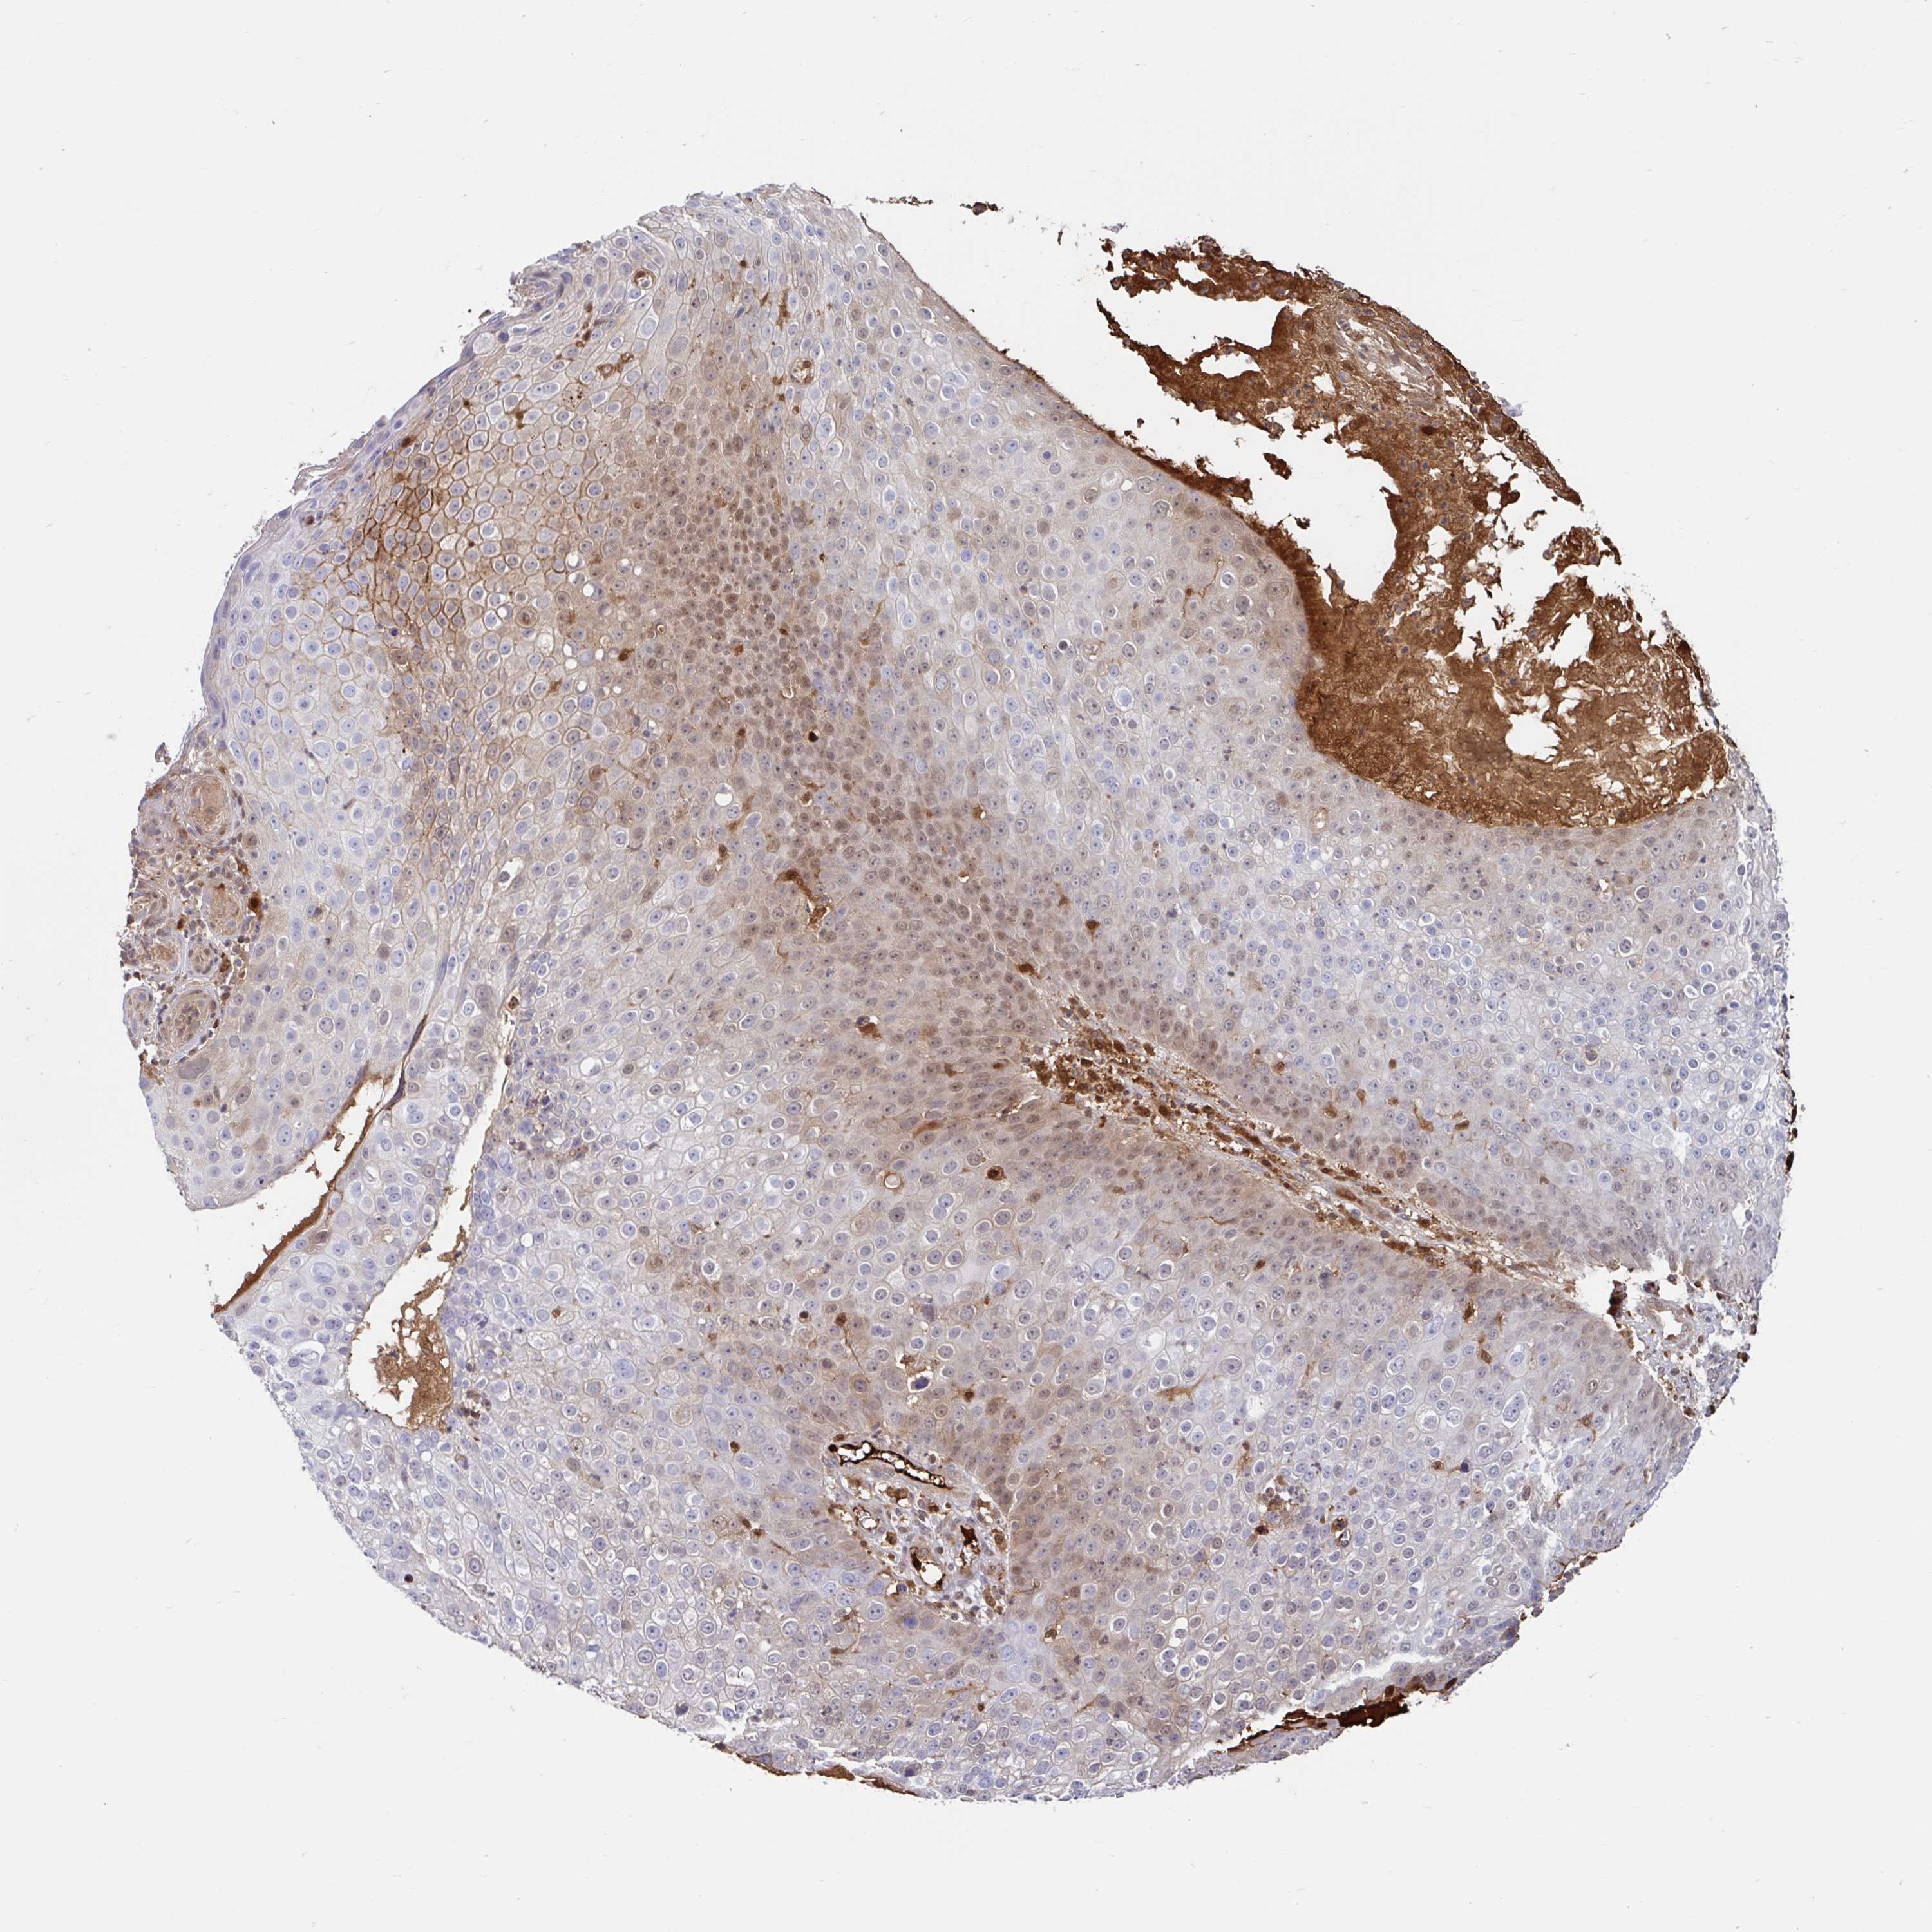

SKIN CANCER - Protein expressioni

A mouse-over function shows sample information and annotation data. Click on an image to view it in a full screen mode. Samples can be filtered based on level of antibody staining by selecting one or several of the following categories: high, medium, low and not detected. The assay and annotation is described here.

Antibody stainingi

Antibody staining in the annotated cell types in the current human tissue is reported as not detected, low, medium, or high, based on conventional immunohistochemistry profiling in selected tissues. This score is based on the combination of the staining intensity and fraction of stained cells.

Each image is clickable and will lead to virtual microscopy that enables deeper exploration of all samples and also displays staining intensity scores, fraction scores and subcellular localization as well as patient and tissue information for each sample.

Antibody HPA042865

Antibody HPA054322

Staining

High

Medium

Low

Not detected

Intensity

Strong

Moderate

Weak

Negative

Quantity

>75%

75%-25%

<25%

None

Location

Nuclear

Cytoplasmic/membranous

Cytoplasmic/membranous,nuclear

Basal cell carcinoma

Squamous cell carcinoma, NOS

Squamous cell carcinoma, metastatic, NOS